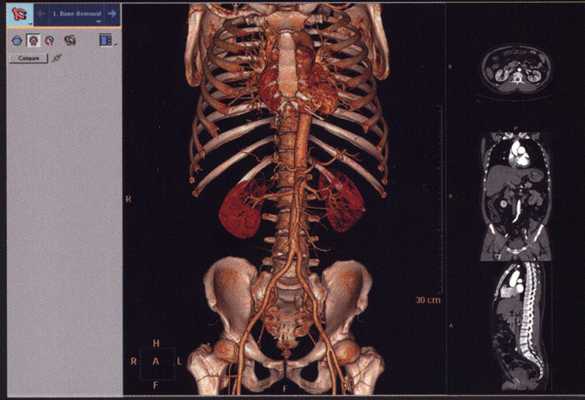

Компьютерная томография скелета

При КТ костей скелета с помощью компьютера получают и выводят на экран монитора изображение различных срезов костей. Срезы могут быть в сагиттальной, горизонтальной и фронтальной плоскостях. Получение коллимированных рентгенограмм увеличивает плотность облучения, рассчитываемую компьютером, и тем самым способствует повышению степени разрешения, а следовательно, и чувствительности и специфичности исследования. Для получения изображений анатомических срезов различной толщины на компьютере обрабатывается информация от облучения сотни тысяч слоев исследуемой ткани или органа.

- Выявление первичной опухоли кости и определение ее размеров, выявление метастазов злокачественных опухолей в кости, а также опухолей мягких тканей, повреждения связок и сухожилий, переломов костей.

Благодаря возможности получения изображений срезов КТ применяют для исследования плечевой кости, позвоночника, бедренной кости и таза. На таких срезах удается избежать наложения теней других структур, которое наблюдается на обычных рентгенограммах. С помощью КТ удается выявить первичные опухоли костей, опухоли мягких тканей, метастазы в кости, а также поражения костей, которые трудно диагностировать другими методами исследования.